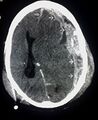

| Beschreibung | Röntgenaufnahme einer Gehirnerschütterung |

| Originaltitel | Dieser CT-Scan ist ein Beispiel für ein subdurales Hämatom durch Trauma; Einzel Pfeile markieren die Ausdehnung des subduralen Hämatoms; Doppel Pfeile markieren die Mittellinenverlagerung |